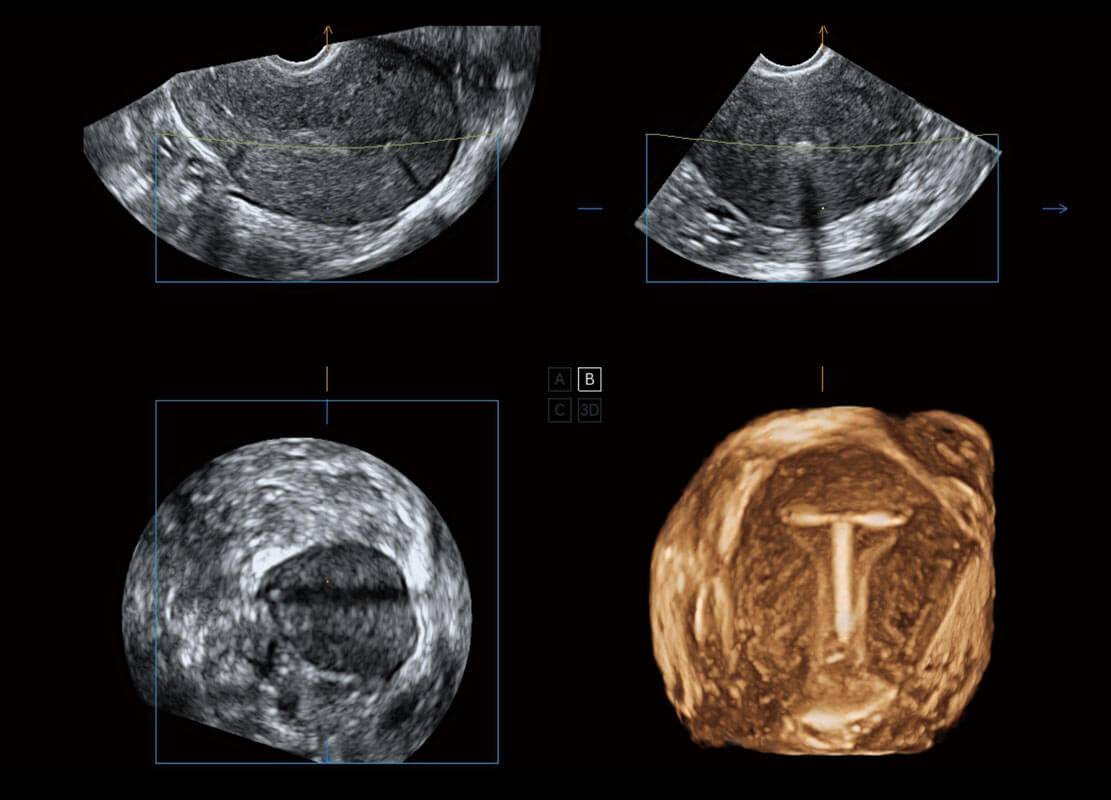

• 腔内三维-宫内节育器

• 腔内三维-光影成像

盆底超声

P60为盆底超声检查提供应用方案,多种腔内及腹部容积探头提供从二维、三维到四维的优异图像品质,实时快速三维容积数据获取,专业的测量工具包等人性化设计,为超声医生诊断提供有力保障。

Lev.Hiat A-r: 16.33 cm2

Lev.Hiat H-r: 53.70 mm

Lev.Hiat W-r: 43.96 mm

Lt-LUG-r: 24.16 mm

Rt-LUG-r: 19.94 mm

S-Pelvic

能够简化盆底检查的操作流程,可在二维模式及三维成像模式下实现一键自动提取出标准切面、自动识别当前切面、自动测量,提升盆底检查的高效性,同时也能让青年医生快捷的获得准确的检查结果。